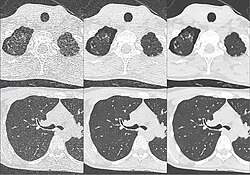

Craniale Computertomographie Abgebildet sind Felsenbein und Nasennebenhöhlen. Aufgrund der hohen Auflösung der Aufnahme des verwendeten 64-Zeilen-CTs sind selbst die Gehörknöchelchen erkennbar. -

Kombination aus multiplanarer Reformatierung und sliding thin slab. Der Bildkursor befindet sich im rechten Lungenflügel. Die sts-Bildstapel werden in Form von MIP-Darstellungen gezeigt (STS-MIP).[52] Links oben befindet sich eine VR-Darstellung der Lunge; sie zeigt einen Blick auf die koronal an Kursorposition geschnittene Lunge. -